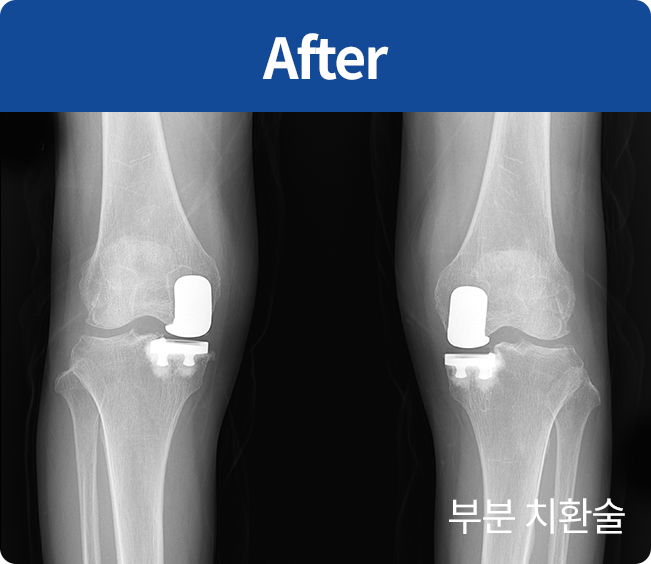

인공 관절 치환술

퇴행성관절염 및 기타 관절손상으로 통증이 심해

정상생활을 할 수 없고 다른 치료나 시술로 효과가 없는 경우에 시행하는 수술법(부분 치환술, 전 치환술)